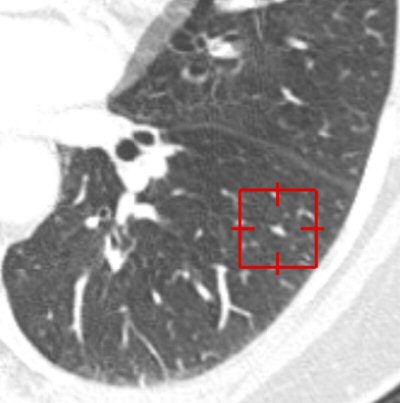

| An elongated nodule missed by all three radiologists during free search. On the axial image (above), the small nodule looks more likely to be a vascular structure with an elongated shape and parallel orientation with adjacent branching vessels. On the coronal image (below), the lesion seems more globular in the craniocaudal direction. 3D volume-rendered image (bottom) presents a discrete nodule between vessels. Although this true-positive nodule was detected by CAD, all three radiologists rejected this nodule with low confidence scores. All images courtesy of Dr. Chin Yi. |